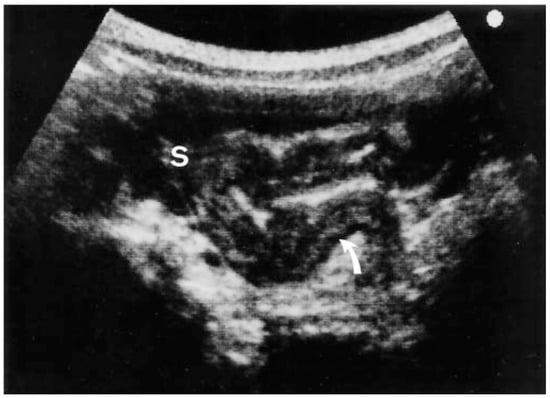

3.2.6. Ultrasonography

3.2.7. Contrast-Enhanced US